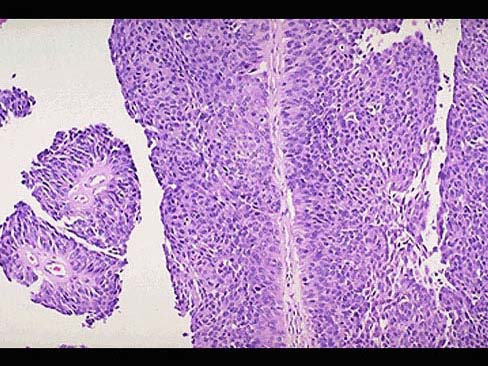

男,65岁。间歇性无痛性肉眼血尿1年。膀胱镜检:膀胱内距输尿管口0.5cm,可见2.5cm×1cm×1cm乳头状肿块,无蒂。静脉肾盂造影可见左肾轻度积水,输尿管全段轻度扩张。行膀胱部分切除后镜检如图所示,下列说法正确的是 ( )

• A.该疾病好发部位为膀胱尖部

• B.该疾病为膀胱透明细胞癌

• C.该疾病手术后不易复发

• D.常见的症状为无痛性血尿

• E.发生在膀胱的肿瘤大部分为良性